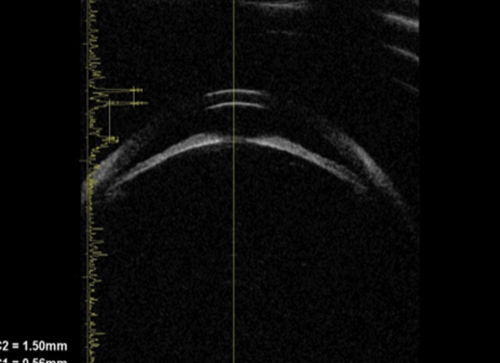

Pupillary block accounts for the majority of cases of primary angle closure. In pupil block, pressure builds up from behind the iris and pushes it anteriorly. UBM can be used to demonstrate that the iris assumes a convex profile due to these pressure differences and this convexity is noted over the entire iris length. Consequent to this, iridocorneal contact results, and the angle is closed (Figure 1).

Figure 1a: Pupil block profile characterised by a convexed profile of the peripheral iris and irido lenticular contact.